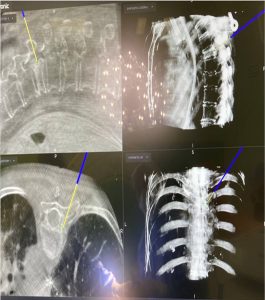

Εικόνα 8 (α,β,γ,δ,) : Πλαγία προεγχειρητική ακτινογραφία (α) της Θωρακο-Οσφυϊκής Μοίρας της Σπονδυλικής Στήλης (Θ-Ο.ΜΣΣ). Παρατηρείται μεγάλη θωρακο-οσφυϊκή κύφωση που προκαλεί διαταραχή της ισορροπίας του κορμού. Προεγχειρητικός σχεδιασμός (β) για την αποκατάσταση οσφυϊκής λόρδωσης στο φυσιολογικό. Μετεγχειρητική προσθιοπισθία (γ) και πλαγία (δ) ακτινογραφία. Παρατηρείται αποκατάσταση της οσφυϊκής λόρδωσης στο φυσιολογικό.